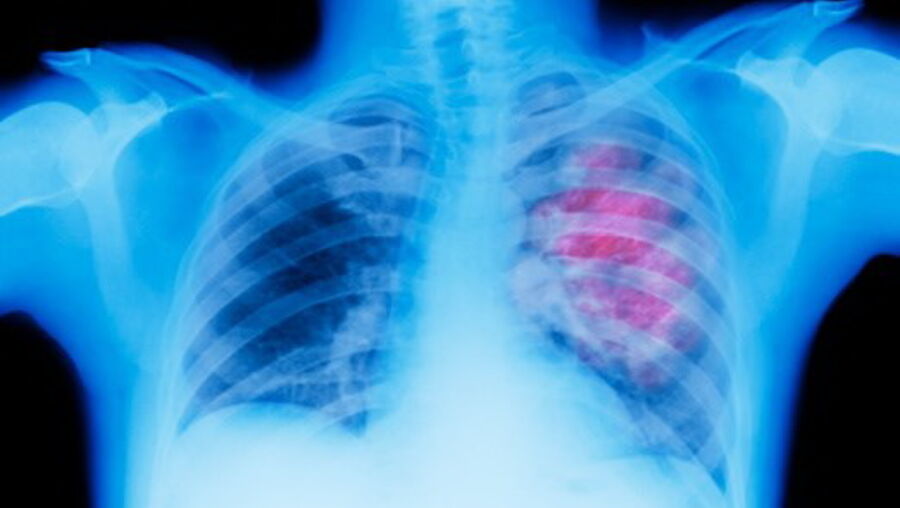

Aliança para combater cancro do pulmão, o que mais mata em Portugal

Várias entidades uniram-se para fundar a Aliança para o Cancro do Pulmão, um projeto que é apresentado esta terça-feira em Lisboa e que visa "fazer frente" ao tumor que não é o mais prevalente em Portugal, mas o que mais mata.

Em declarações à agência Lusa, o oncologista António Araújo explicou que a ideia partiu do que se observou noutros países em que "várias entidades e vários profissionais se uniram no sentido de combater uma doença que é altamente prevalente na sociedade, o cancro do pulmão, e que tem um comportamento biológico muito agressivo e, portanto, tem uma taxa de mortalidade muito elevada".